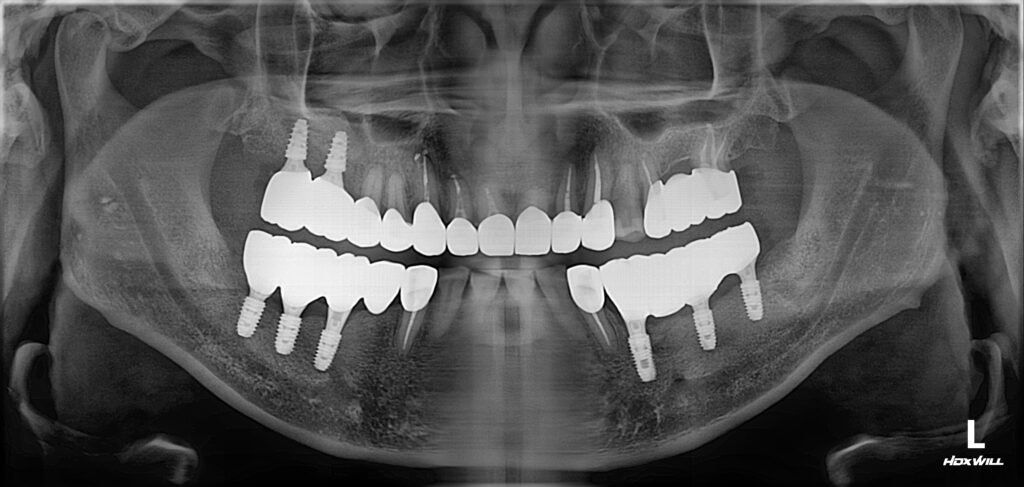

상태는 위와 같았습니다. 아래 앞니를 제외하고는 전부다 문제가 있는 상황이었습니다.

1. 치아 상실

2. 깊은 충치

3. 심한 잇몸 염증

4. 치아 부러짐 등

발생할 수 있는 모든 문제점들이 다 발생해 있었습니다.

위와 같이 임플란트를 심고 뼈가 붙는 시간을 3개월 기다렸습니다.

상악동 거상술과 (연두색 점선) 뼈이식(하늘색 점선)을 동반하여 임플란트를 식립하였고

임플란트가 붙는 기간 동안에 어금니 신경치료까지 진행하였습니다.

위와 같이 치료가 완료되었습니다. 상당히 깔끔하게 잘 치료되었네요. 총 치료 기간은 4개월 소요되었습니다.